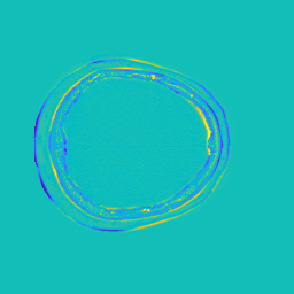

Model-based treatment planning for transcranial ultrasound therapy typically involves mapping the acoustic properties of the skull from an x-ray computed tomography (CT) image of the head. Here, three methods for generating pseudo-CT images from magnetic resonance (MR) images were compared as an alternative to CT. A convolutional neural network (U-Net) was trained on paired MR-CT images to generate pseudo-CT images from either T1-weighted or zero-echo time (ZTE) MR images (denoted tCT and zCT, respectively). A direct mapping from ZTE to pseudo-CT was also implemented (denoted cCT). When comparing the pseudo-CT and ground truth CT images for the test set, the mean absolute error was 133, 83, and 145 Hounsfield units (HU) across the whole head, and 398, 222, and 336 HU within the skull for the tCT, zCT, and cCT images, respectively. Ultrasound simulations were also performed using the generated pseudo-CT images and compared to simulations based on CT. An annular array transducer was used targeting the visual or motor cortex. The mean differences in the simulated focal pressure, focal position, and focal volume were 9.9%, 1.5 mm, and 15.1% for simulations based on the tCT images, 5.7%, 0.6 mm, and 5.7% for the zCT, and 6.7%, 0.9 mm, and 12.1% for the cCT. The improved results for images mapped from ZTE highlight the advantage of using imaging sequences which improve contrast of the skull bone. Overall, these results demonstrate that acoustic simulations based on MR images can give comparable accuracy to those based on CT.